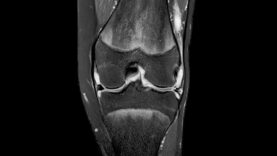

Tophaceous gout is characterized by collections of densely packed urate crystals, which are occasionally calcified, in connective tissues and accompanied by a chronic inflammatory response. These collections can be visible and/or palpable but are usually not painful or tender; they can be present on the ears or in the soft tissues, including articular structures, tendons, bursas, or bone. Tophi may be detected with ultrasonography, dual-energy CT (DECT), or MRI. It is likely that many patients with gout and sustained hyperuricemia have a much larger burden of urate crystal deposits than is suspected by clinical examination alone.